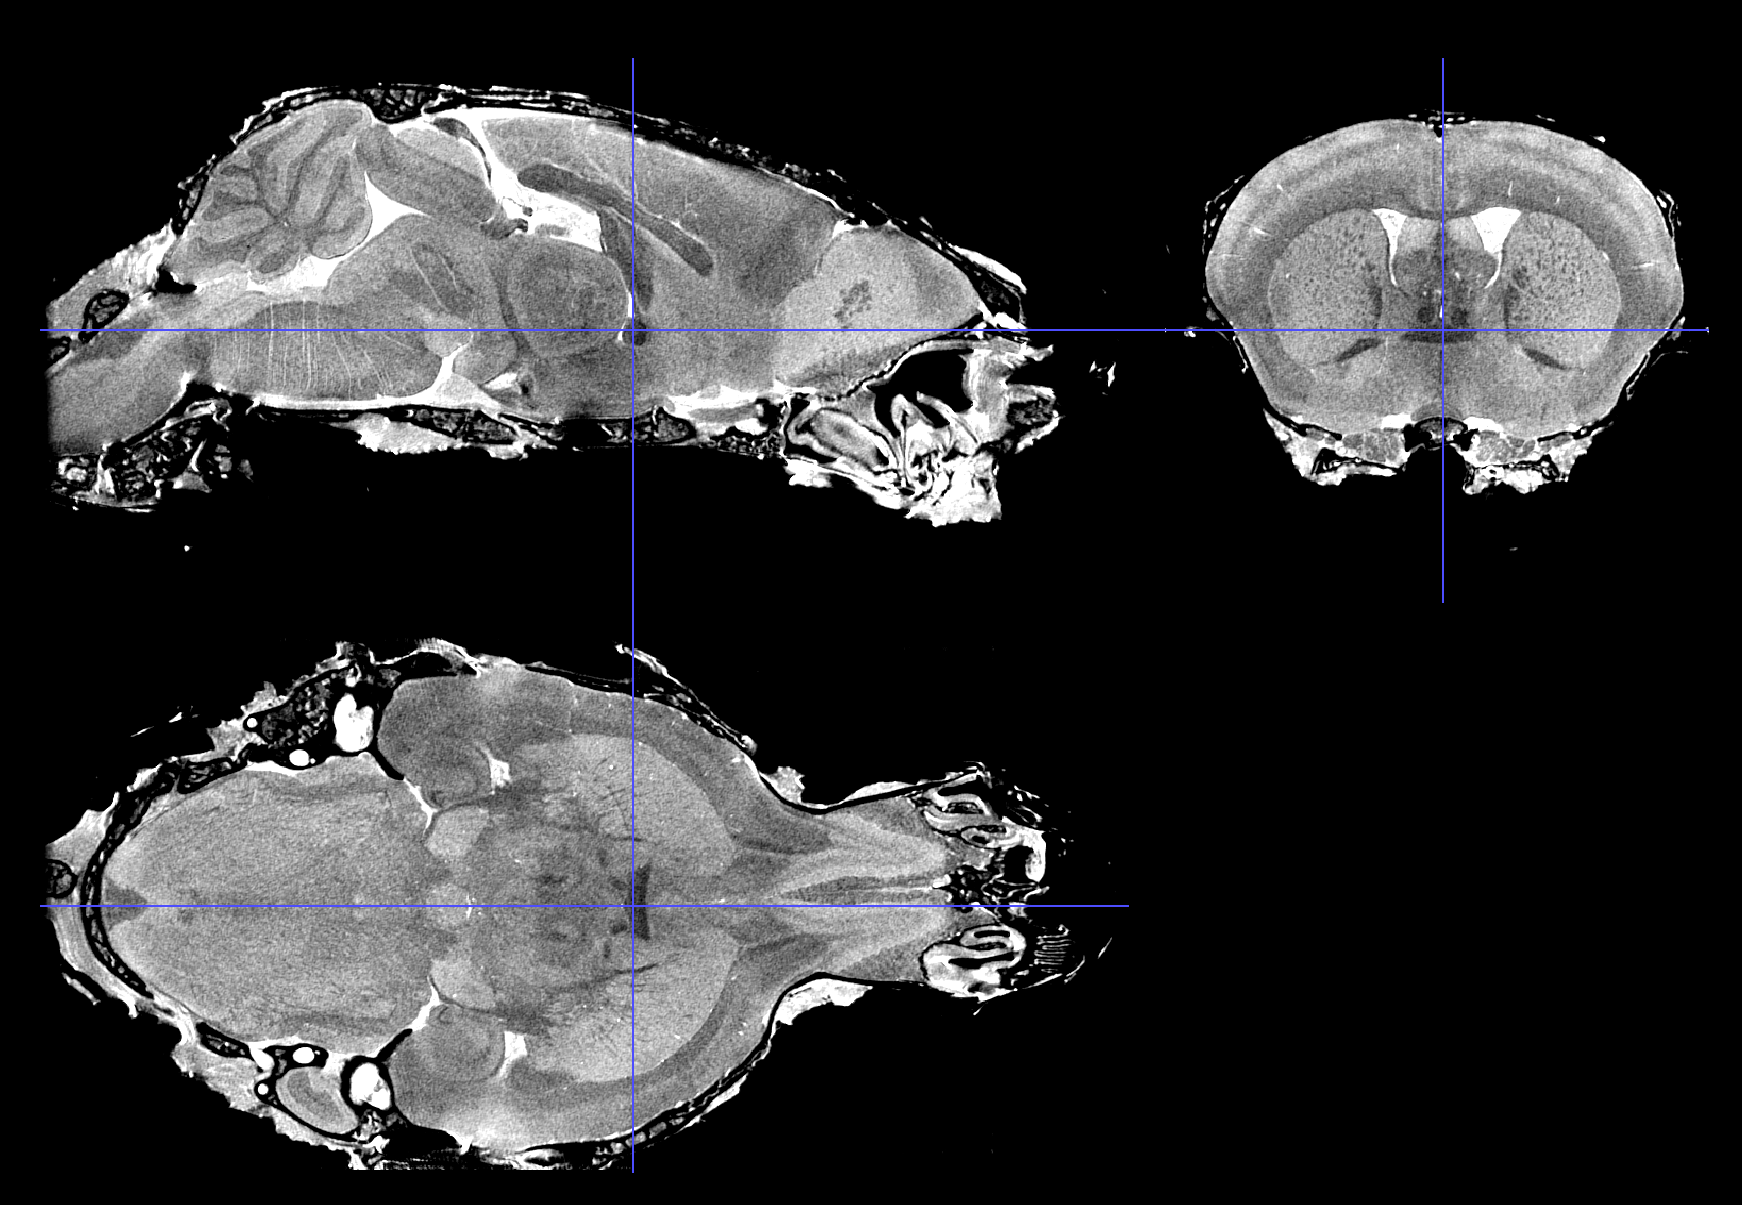

Scalable Brain Atlas  Coronal3d

Mouse - Allen Mouse Brain Common Coordinate Framework version 3

About this atlas

The defining citations for this atlas template are:

1. Lein ES, Hawrylycz MJ, Ao N, et al. (2007) "Genome-wide atlas of gene expression in the adult mouse brain." Nature 445(7124):168-76. [doi 10.1038/nature05453]